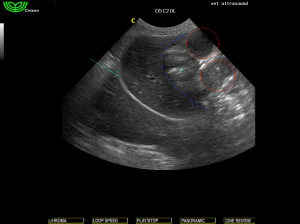

πράσινο βέλος διάφραγμα, η μπλέ γραμμή αφορίζει το ήπαρ, ο αστερίσκος δείχνει το στομάχι, οι κύκλοι περιβάλουν το διατεταμένο λεπτό έντερο.